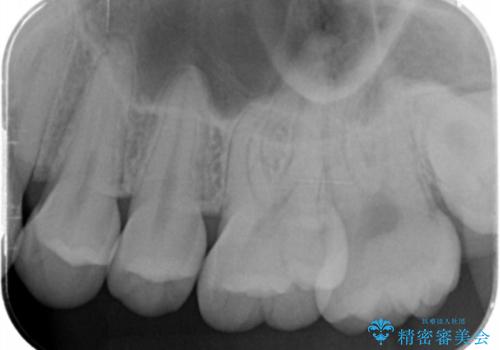

奥歯の黒いのが気になる。

- 奥歯が黒いとの事で来院。

歯の表面がう蝕になっていたので拡大鏡でう蝕を除去し、e-maxインレー(セラミックインレー)で治療を行いました。